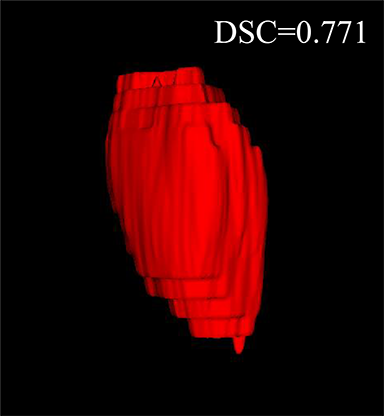

Comparison with ground truth. Some predicted results of MMFNet are shown in 2D images and 3D images in Figure 7 and Figure 8. As shown in these figures, although the shape and size of NPC are varied from each other, MMFNet can still accurately determine the regions of NPC and obtain the accurate contours of tumors. Through analyzing 2D images in figure 7, MMFNet has a capacity to fuse multi-modality MRI to reduce the confusion brought by intensity’ similarity between nearby tissues and NPC. The values of , and of MMFNet are shown in Table 1. MMFNet can reach the best results with , and .

Comparison with related works. Table 1 reports the values of , and for different methods. Predicted masks of different methods are illustrated in Figure 9 and Figure 10, which respectively present results in 2D and 3D images. Through comprehensively analyzing these results, the proposed MMFNet actually have the following properties:

(i) It directly fuses 3D MRI images rather than 2D slices. Thus, it can effectively use meaningful information from neighboring slices of MRI to realize NPC segmentation. As shown in Table 2, MMFNet can bring , and improvements in and compared to the best method based on 2D images (Multi-modality patch-based CNN). And Figure 10 shows that 3D-based methods have less isolated regions (false positives) than 2D-based ones.

(ii) It segments NPC by fusing multi-modality MRIs with the multi-encoder network. Thus, it can learn complementary and interdependent features from different modalities of MRI for final decisions. Additionally, comparing with input-level fusion networks and decision-level fusion networks, layer-level fusion networks (including MMFNet) can effectively capture informative features from different modalities of MRI and fuse low-level features and high-level features.

(iii) It uses a fusion block to fuse low-level features from different modalities of MRI and prepare these low-level features for the fusion with high-level features. Thus, it can more effectively fuse information from various sources. It also uses the self-transfer strategy to initialize the netwerk. Hereby, it can stimulate encoders to make full mining of meaningful features from modality-specific MRI. And it finally improve base multi-encoder-based network (Merging encoders’ fetures) by , and in and .